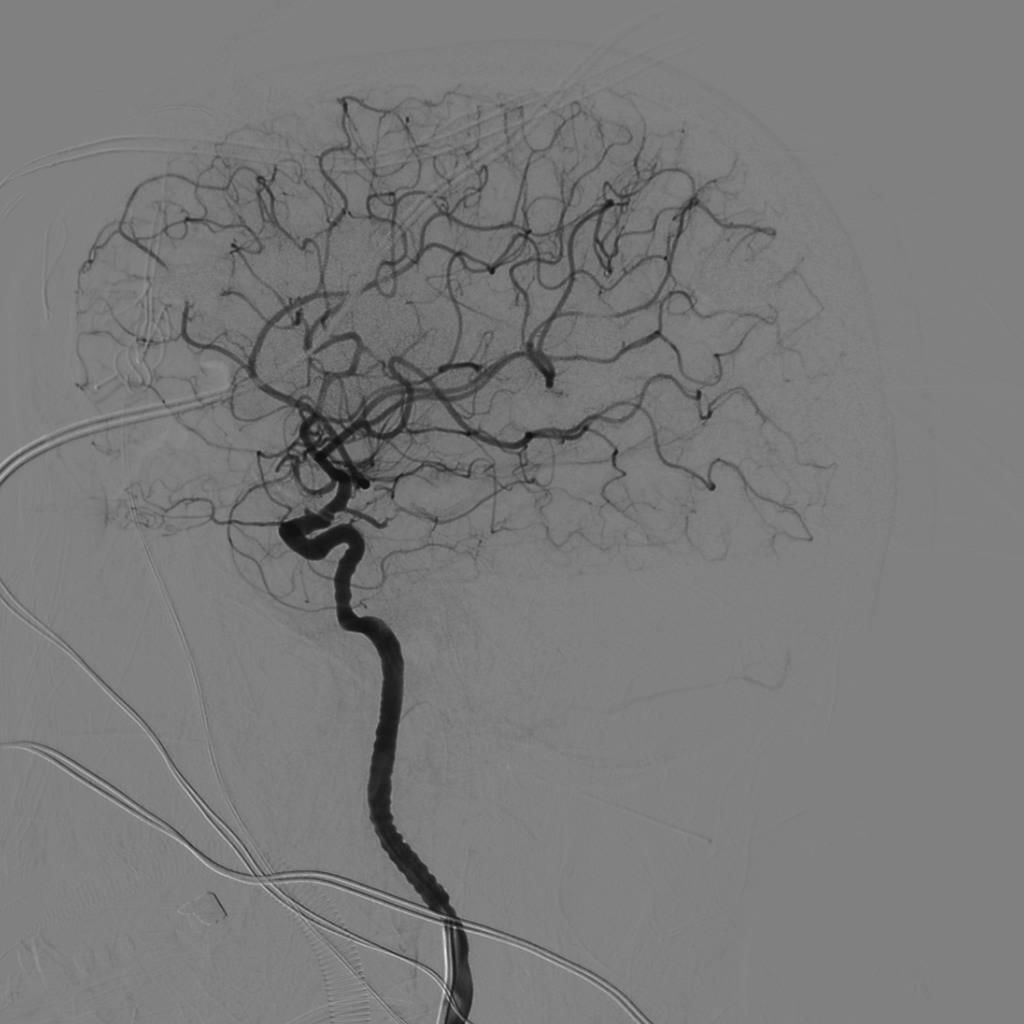

再次探查动脉瘤发现瘤体表面张力明显下降,探针分离瘤颈,以2枚直动脉瘤夹792+760夹闭瘤颈。解除球囊阻断后,动脉瘤表面张力无回升,穿刺瘤体无活动性出血。荧光造影提示瘤体无显影,载瘤动脉血流通畅,无明显狭窄,各分支保留完好。切除部分瘤体,视神经减压。DSA复查提示动脉瘤夹闭满意,全脑血管通畅后关颅。(球囊阻断时间约10分钟)

夹闭后复查DSA